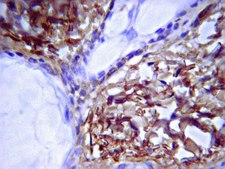

Immunohistochemistry:

1:40 dilution of a previous lot for immunofluorescent staining of frozen mouse skin and liver tissues.